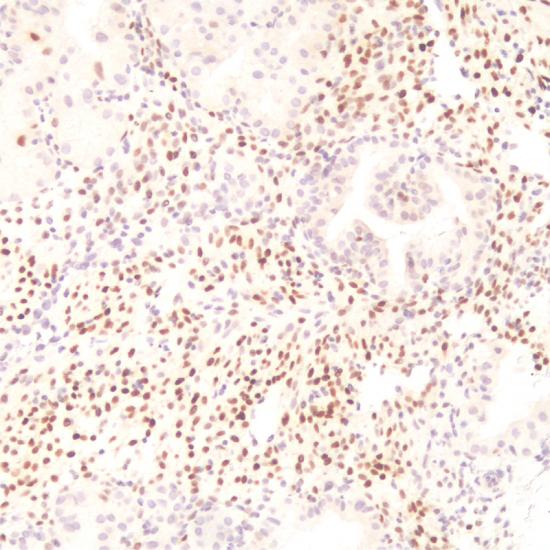

p57抗體試劑(免疫組織化學) 閩廈械備20180286號

p57是一種細胞周期依賴的激酶抑制劑和抑癌基因,定位于染色體11P15.5。在妊娠宮內膜中,蛻膜細胞p57表達陽性,但是分泌腺體中陰性。正常胎盤中,>30%滋養(yǎng)葉細胞、絨毛間質及絨毛中央滋養(yǎng)層細胞島細胞核表達該抗體,合體滋養(yǎng)層陰性。完全性葡萄胎均由父系DNA產(chǎn)生,p57不表達;部分性葡萄胎有父母雙方DNA,表達p57,故該抗體可以用于研究完全性及部分性葡萄胎。